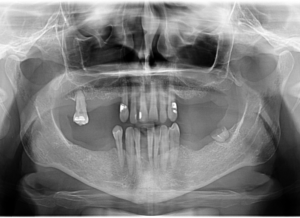

În radiografia atașată mai jos puteți observa radiografia pacientei, ajunsă deja la etapa lucrărilor finale: